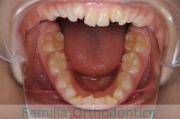

- ≫治療前

上顎

下顎

前歯の関係など

右側

正面

左側